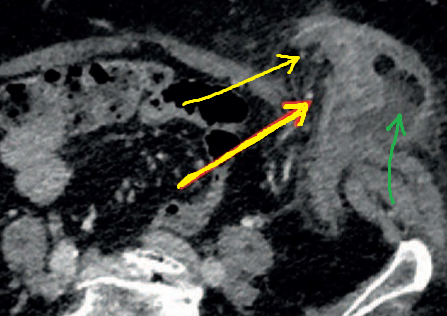

Κίτρινα βέλη — Φλεγμαίνουσες εκκολπώσεις στο εξω-κοιλιακό εντερικό τμήμα. Πράσινο βέλος — Υγρή συλλογή (Ευγενική παραχώρηση Dr. V. Penopoulos)